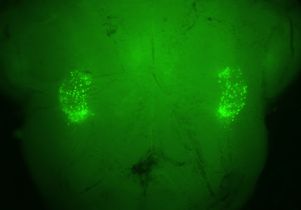

The researchers decided to look in the brain’s breathing center in the brainstem. They analyzed the genes in those cells and found that a few hundred of them generate one of two chemicals that allow them to communicate with the “preBötzinger Complex,” a bundle of a few thousand neurons known to control the rate and rhythm of respiration.

When the researchers injected these previously isolated compounds, known as “Nmb” or “Grp”, into the mice’s brains, they found that the mice sighed 10 times more often per hour. When the researchers blocked the Nmb peptide, the mice sighed only half as often as they had originally; inhibiting the pathways made the mice almost stop sighing altogether. None of these changes affected the mice’s normal breathing.